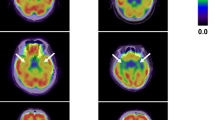

Representative PET-CT images of peripheral angiogenesis acquired 1 week after surgical ligation are shown in Fig. 6. Confirmed by biodistribution studies, PET-CT images obtained 1 hr after intravenous injection of the radiotracer were of excellent quality and demonstrated “hot spots”–of increased 64Cu-NOTA-PEG4-cRGD2 uptake within the ischemic hindlimb–whereas the non-ischemic muscle showed no significant uptake. Moreover, VOI-based image analysis of PET-CT images (see Fig. 6) correlated well (R2 = 0.9602) with postmortem 64Cu-NOTA-PEG4-cRGD2 activities in the hindlimb muscle sections measured using gamma well counting immediately after PET-CT imaging (see Fig. 6).

PET-CT imaging analysis. (A) Representative in vivo PET-CT images of peripheral angiogenesis 1 week after surgical ligation of the right femoral artery. One hour after intravascular injection of 64Cu-NOTA-PEG4-cRGD2 a significant uptake of the radiotracer (“hot spot”) was observed in the ischemic hindlimb. (B) For the image analysis, volumes-of-interests (VOIs) were drawn on CT images of ischemic and non-ischemic hindlimbs (left) followed by segmentation of hindlimb muscles (middle). These irregular VOIs were placed on PET images to calculate the radiotracer’s uptake (expressed in %I.D./g tissue, right). (C) Correlation between the two methods (PET-CT and gamma well counting) used to measure radiotracer uptake in mice hindlimbs showed a strong linear correlation (R2 = 0.9602, solid line).

Most importantly, we found a significant (P < 0.05) reduction of 64Cu-NOTA-PEG4-cRGD2 uptake in all muscle segments (distal and proximal) of diabetic animals when compared to the non-diabetic control segments (see Fig. 7). Quantitative analysis of PET-CT images confirmed this result, indicating that DM mice had significantly lower %I.D./g in their distal ischemic tissue than non-diabetic mice. PET imaging showed a significant increase in the retention of 64Cu-NOTA-PEG4-cRGD2 in the ischemic (relative to non-ischemic) hindlimbs, which demonstrates the probe’s specificity to areas of active angiogenesis and α V β3 expression. Together, these findings indicate that molecular imaging with 64Cu-NOTA-PEG4-cRGD2 is suitable to quantitatively asses different angiogenic responses in DM and non-DM environments.

Analysis of 64Cu-NOTA-PEG4-cRGD2 retention in the hindlimbs of DM and non-DM mice 1 week after surgical ligation of the right femoral artery. Overall there was a significant (#P < 0.05) increase in 64Cu-NOTA-PEG4-cRGD2 retention in the distal segments of the ischemic relative to the non-ischemic hindlimbs, as well as a significant (*P < 0.05) decrease in the distal ischemic hindlimb of DM mice compared to non-DM controls.